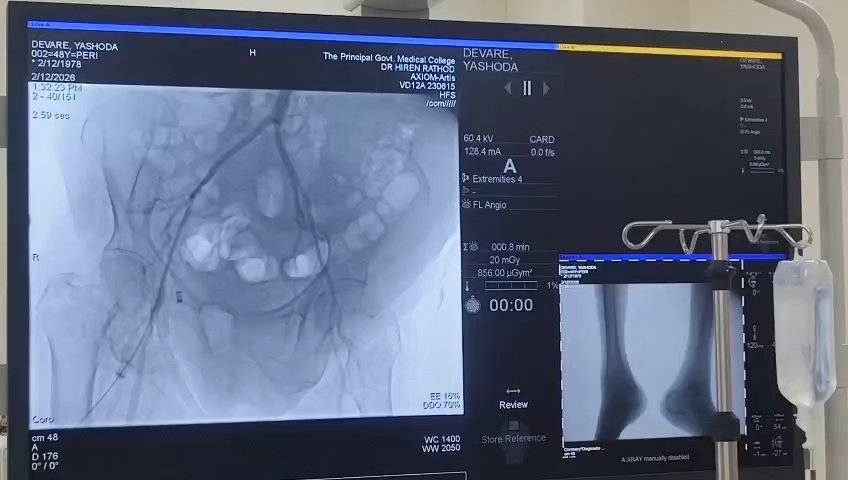

દક્ષિણ ગુજરાતના લાખો દર્દીઓ માટે એક મોટી રાહતના સમાચાર સામે આવ્યા છે.New Civil Hospitalમાં સુપર સ્પેશિયાલિટી પ્રોજેક્ટ હેઠળ અદ્યતન કેથેટરાઈઝેશન લેબોરેટરી કેથલેબ શરૂ કરવામાં આવી છે. હવે હૃદયના બ્લોકેજથી લઈને માથાથી પગ સુધીની વિવિધ રક્તવાહિનીઓના ગંભીર રોગોનું નિદાન અને સારવાર સુરતમાં જ શક્ય બનશે.અંદાજે રૂ. ૩ કરોડના ખર્ચે સ્થાપિત આ અદ્યતન બાયપ્લેન મશીન દ્વારા એન્જિયોગ્રાફી, એન્જિયોપ્લાસ્ટી, સ્ટેન્ટિંગ અને પેસમેકર ઈમ્પ્લાન્ટેશન જેવી જીવનરક્ષક સારવાર મળશે. ખાસ વાત એ છે કે એન્ડોવાસ્ક્યુલર ઈન્ટરવેન્શનલ રેડિયોલોજી પદ્ધતિ દ્વારા હવે મોટા ઓપરેશન વિના, નાનાં છિદ્ર મારફતે કેથેટર દાખલ કરી સ્ટેન્ટિંગ, એમ્બોલાઈઝેશન અને થોમ્બેક્ટોમી જેવી પ્રક્રિયાઓ કરી શકાશે. એટલે કે દર્દીઓને ઓછું દુખાવો, ઓછી જોખમ અને ઝડપી આરોગ્યલાભ મળશે.

કેથલેબ શરૂ થવાના પહેલા જ દિવસે મગજ અને પગની નસોના દર્દીઓની સફળ એન્ડોવાસ્ક્યુલર સારવાર કરવામાં આવી હતી. હવે નસ પાતળી થવી, નસમાં ફુગ્ગો (એન્યુરિઝમ) બનવો, નસનો ગુચ્છો બનવો અને વધુ બ્લીડિંગ થવા જેવી ગંભીર પરિસ્થિતિઓમાં તાત્કાલિક સારવાર ઉપલબ્ધ રહેશે.આ ઉપરાંત થાઇરોઈડ અને પ્રોસ્ટેટ જેવી કેન્સર સિવાયની સાદી ગાંઠોની સારવાર પણ અહીં શક્ય બનશે. ચોક્કસ પ્રકારના કેન્સરના દર્દીઓમાં જ્યાં સર્જરી શક્ય નથી, ત્યાં ગાંઠ નાની કરવા માટે કેમો-એંબોલાઈઝેશન જેવી અદ્યતન સારવાર પણ આપવામાં આવશે.કેથલેબના પ્રારંભ પ્રસંગે સુપ્રિન્ટેન્ડન્ટ ડૉ. ધારિત્રી પરમાર, RMO ડૉ. કેતન નાયક, ઈન્ટરવેન્શન ન્યુરોલોજિસ્ટ ડૉ. પ્રયાગ મકવાણા, રેડિયોલોજી વિભાગના પ્રો. ડૉ. પૂર્વી દેસાઈ ઈન્ટરવેન્શન રેડિયોલોજિસ્ટ ડૉ. હિરેન રાઠોડ સહિત આરોગ્ય ક્ષેત્રના અગ્રણીઓ ઉપસ્થિત રહ્યા હતા.